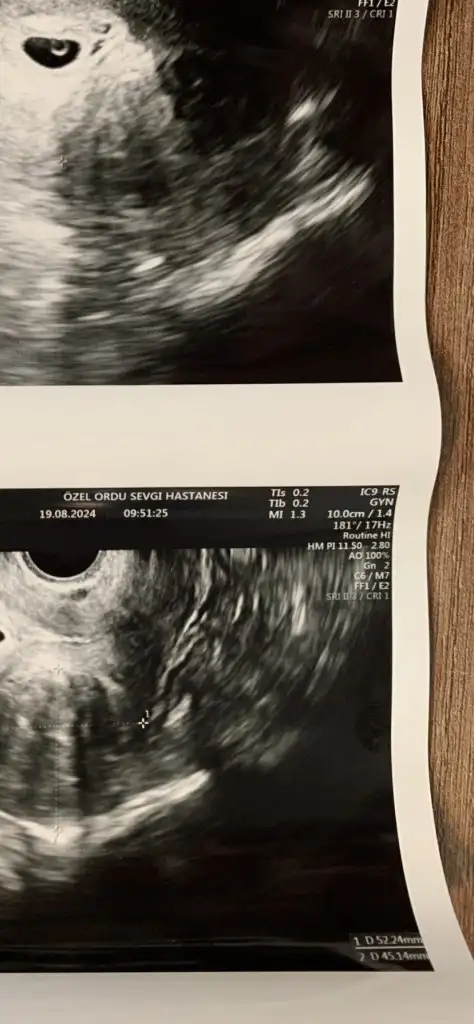

Başka hastanede GS imiş bak kesenin üzerinde yaziyo hem de sağ alt köşede yaziyo boyu

Eklentiler

• 20240809_123712.webp

20240809_123712.webp

23,4 KB · Görüntüleme: 178

Hastaneye özgü bir harfleme sistemi var sanırım da ben kese boyu olabilecek bir rakam goremedim henuz

Galiba bende baktım baktım bir bilgiye ulaşamadım kendi merkezim normal dedi ama kalbi görebilirdim göremedim 6+0 da üç gün gerideymişiz iki hafta sonra kendi doktoruma gidicem çok da ilaç alıyorum bakalım gelişimi iyi olacak mı ilk haftalarda geriden gelenler pek iyi olmuyor benim çok değil yine de bakalım